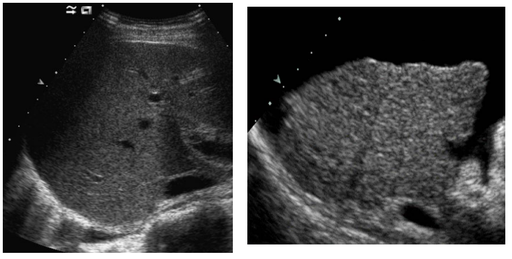

Initiation à l'échographie abdominale

Cliniciens : Formation Continue

DANSE E. - UCL

Digestif US